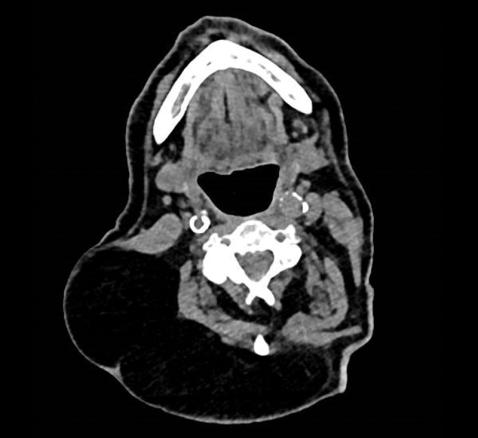

Lipome cervical

Le scanner note des images de densité graisseuse (- 100 UH).